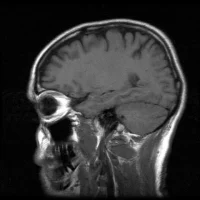

Conventional imaging techniques, such as CT scans and MRI, cannot detect the subtle damage to axons (the nerve fibers that constitute the brain’s white matter) that is associated with concussions.

But in a previous study, Dr. Lipton and his colleagues demonstrated that DTI can detect concussion-related damage to axons by “seeing” the movement of water molecules along axons, which allows researchers to measure the uniformity of water movement (called fractional anisotropy, or FA) throughout the brain. Finding a low FA brain region, for example, indicates structural damage that has impeded water movement in that area.

In the current study, Dr. Lipton tested whether brain abnormalities identified on DTI of individual concussion patients could distinguish between those patients who will eventually recover and those who will not. DTI was performed on 39 patients diagnosed with mild TBI by an emergency room physician within 16 days of the initial injury and on 40 healthy controls. Patients were also assessed for cognitive function, post-concussion symptoms and health-related quality of life measures. A year later, 26 of the concussion patients returned for follow-up assessments.